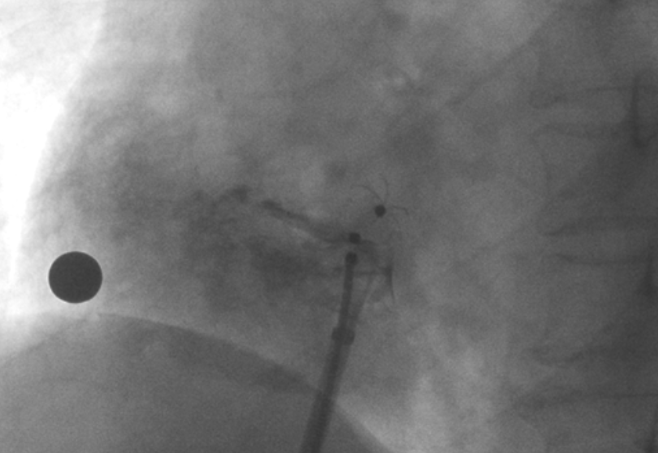

術(shù)中造影顯示患者為PFO且長隧道型,目前市場上已商業(yè)化的PFO封堵器難以滿足該患者解剖結(jié)構(gòu)封堵需求。迪創(chuàng)醫(yī)療自主研發(fā)的OmniSeal PFO封堵器自適應(yīng)性雙盤貼合設(shè)計(jì)能廣泛適應(yīng)不同PFO隧道長度的解剖結(jié)構(gòu)和形態(tài),其雙盤外包覆式阻流和隧道內(nèi)填充阻流相結(jié)合的雙重阻流設(shè)計(jì),可為此患者實(shí)現(xiàn)有效封堵。與此同時(shí),OmniSeal首創(chuàng)的完全可穿刺式設(shè)計(jì),也為此患者最大程度地保留了房間隔區(qū)域穿刺通道,以實(shí)現(xiàn)全兼容未來可能的左心系統(tǒng)二次介入術(shù)。術(shù)終造影和心臟超聲顯示封堵完全、效果良好。作為OmniSeal的首例臨床應(yīng)用,本次手術(shù)的順利完成和優(yōu)異效果充分體現(xiàn)了產(chǎn)品的設(shè)計(jì)創(chuàng)新優(yōu)勢。

造影顯示PFO封堵完全,無殘余分流, 試驗(yàn)器械充分舒展并貼合良好